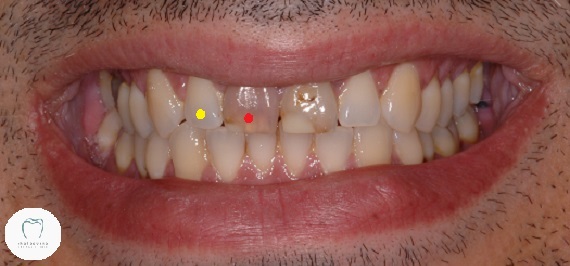

I completed this really interesting dental crown case last week. (Well, I hope I’ve completed it. More on that later!) This gentleman presented last year in pain and with two dark teeth at the front that looked like this:

Both teeth are badly discoloured and heavily filled. His upper right central (red dot) tooth was hurting. A lot. If we tapped on it, there was even more pain. So we took an X-ray and found this:

We decided to brighten up the other teeth first with some teeth whitening. Once the new tooth colour had been given time to stabilise, we finally restored this smile with a pair of all-ceramic dental crowns for maximum aesthetics.

Here’s the final before and after photos:

Needless to say he’s delighted with the result!